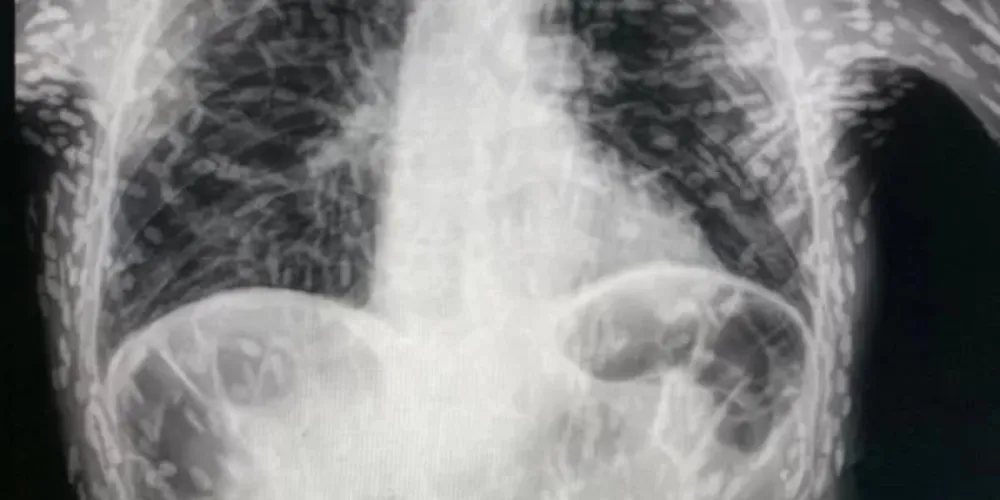

Exame de raio-x revela ovos de tênia em tórax de paciente

Ovos de tênia encontrados no tórax já estavam mortos e calcificados -

O médico Vitor Borin de Souza, residente pelo Hospital das Clínicas de Botucatu, compartilhou pelas redes sociais a imagem chocante da radiografia de um paciente com um quadro de cisticercose, doença parasitária causada pela ingestão dos ovos de tênia.

Segundo Souza, o paciente apresentava tosse constante há dois meses quando o exame foi solicitado. Os ovos de tênia encontrados no tórax já estavam mortos e calcificados, ou seja, não apresentavam risco a ele.